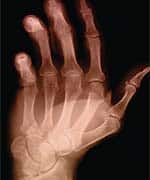

One in three adults in the US—approximately 66 million people—suffer from arthritis or symptoms of chronic joint pain, according to the Arthritis Foundation.2 One of the most prevalent chronic health problems, arthritis is the leading cause of disability among Americans over the age of 15. Second only to heart disease as a cause of work disability, arthritis limits simple everyday activities such as walking, dressing, and bathing for more than 7 million Americans. Arthritis is responsible for an estimated 39 million physician visits and more than a half million hospitalizations each year.2 Like fibromyalgia, arthritis is usually a chronic condition, characterized by pain, stiffness, inflammation, swelling, and even destruction of the joints. The severe, chronic pain that often accompanies conditions like fibromyalgia and arthritis can greatly compromise a person’s quality of life. Moreover, chronic pain can lead to depression, increased stress, and reduced activity levels, which can further exacerbate symptoms, producing a vicious cycle of worsening pain, depression, and inactivity. While many people suffering from arthritis and fibromyalgia seek relief from over-the-counter medications and prescription nonsteroidal anti-inflammatory drugs (NSAIDs), others avoid these drugs for fear of the adverse side effects associated with many of them. It was precisely this predicament that led H. Edward Troy, PhD, to devote 14 years of his life to developing an all-natural, topical cream that could provide fast, safe, effective relief from joint and muscle pains. | ||||

A Personal Quest for Pain ReliefDr. Troy had long struggled with his own severe arthritis pain. As the head research pharmacologist for a major international pharmaceutical company, he was well acquainted with investigations of new and innovative drugs—and all too aware of the limited options available to arthritis sufferers. Like most people with arthritis, he had tried counter-irritant creams and capsaicin-based products, as well as NSAIDs like aspirin and ibuprofen. Eventually, he resorted to more powerful steroidal drugs such as prednisone. Yet none of these products provided truly effective relief for his arthritis, and some had harmful side effects as well. Dr. Troy thus decided to focus his career on developing an analgesic that could offer significant pain relief without dangerous side effects. He knew that doctors and other medical practitioners had long used certain topical preparations to provide therapeutic relief for the pain and discomfort of arthritis. He theorized that through trial and error, these compounds could eventually be isolated and combined in a compatible, balanced, all-natural formula. Identifying the ideal combination of ingredients proved maddeningly elusive. Some nutrients lacked sufficient effectiveness, while others irritated the skin or had unacceptable odors. Motivated by his own arthritis, Dr. Troy persevered and continued to explore ever more esoteric nutrient blends. He eventually achieved success with a proprietary formula that combines more than 18 different natural compounds. Dr. Troy’s extraordinary quest lasted 14 years and an astounding 1,221 failed attempts to find the ideal blend. When he finally found the formulation that worked, he therefore named it Natural Relief 1222. Natural Relief 1222 is a patented, all-natural analgesic cream that contains no traditional counter-irritants or capsaicin. Its proprietary combination of botanical and organic ingredients provides effective relief without the icy-hot sensations and overpowering odors associated with over-the-counter analgesics. Natural Relief 1222 does not cause the gastrointestinal side effects associated with the use of aspirin and other NSAIDs. Its patented blend of nutrients is the only pharmaceutically prepared analgesic compound that has been found in human studies to provide rapid, safe, effective pain relief in various body tissues—without side effects. Among the ingredients contained in Natural Relief 1222’s patented, proprietary formula are shark liver oil, deodorized garlic oil, vitamin E, and other complementary nutritional and botanical extracts. According to Dr. Troy, the ingredients in Natural Relief 1222 may work through several mechanisms of action. The first is by neutralizing free radicals, the unstable molecules that can damage everything from blood vessel walls to the cartilage tissue surrounding joints.3 Antioxidants neutralize free radicals, and Natural Relief 1222 contains vitamin E, a powerful fat-soluble antioxidant,4 as well as shark oil-derived omega-3 fatty acids,5 which are known to confer potent anti-inflammatory benefits.6 Natural Relief 1222 also contains two botanically based extracts, Bryonia alba 6x and Rhus toxicodendron 6x. Bryonia alba 6x traditionally is used to treat aching muscles, stitching pains, pressure and sinus headaches, and painful stiffness in the nape of the neck and lower back.7 It is also indicated for joint pain, joints that are red, swollen, or stiff, and knee pain.7 Rhus toxicodendron 6x is used to manage pain in the joints and tendons, muscle sprains and strains, tenderness of the knee joints, lower back pain, stiffness of the neck, arms, and legs, and pain in the jaw.8 Three Clinical Trials Confirm EffectivenessThree separate clinical trials have documented the effectiveness of Natural Relief 1222. The San Diego-based California Research Foundation, a private organization that has investigated drugs and supplements for more than 60 pharmaceutical companies, conducted a two-week study of 48 patients with rheumatoid arthritis and/or osteoarthritis. The volunteers were divided into two groups of equal age, duration of arthritis, and baseline condition. Half of the subjects were given Natural Relief 1222 and the other half received a placebo cream. After the patients were screened and their symptoms noted, the creams were applied and the patients remained in the clinic for 30 minutes to rate their pain relief. They were then instructed to apply the cream to their arthritic areas four times a day—upon awakening and at lunch, dinner, and bedtime—for two weeks. At a second visit seven days later, the study investigators and test subjects assessed the changes, if any, in arthritic symptoms. This procedure was repeated at the end of the study period. Statistical comparisons of the two groups show that those using Natural Relief 1222 had a significantly higher improvement score, beginning 30 minutes after the first treatment. Of the 24 patients who used Natural Relief 1222, 13 (54.2%) reported improvement in their limitation of motion, compared to just 3 of 24 (12.5%) in the placebo group. The researchers also noted an absence of systemic side effects during the study.9 In a second study led by Dr. Paul A. Repicky, 72 subjects rated Natural Relief 1222’s effectiveness in relieving arthritis pain, joint pain, and muscle stiffness.10 The subjects were selected from a group of patients who were using another product for symptom relief at the study’s onset. They were asked to rate the effectiveness of the analgesic or anti-inflammatory medication they had been using, on a scale of 1 (least effective) to 4 (most effective). They were then asked to stop the use of their medications before beginning application of Natural Relief 1222 to the affected area once daily for three days. After three days, they were asked to rate the effectiveness of Natural Relief 1222 using the same scale as before. The results confirmed the superiority of Natural Relief 1222. More than 80% of the participants ranked this cream as more effective than the medication they had been using before. Eighty-three percent said it was the most effective treatment for their pain, while 82% found it most effective for increasing their range of motion. In addition, 85% of patients with arthritis ranked it as best for pain, while 80% of the subjects with soft tissue injuries gave it top marks for pain relief. The speed of action was impressive as well, with many patients reporting an alleviation of symptoms after the initial application. None of the subjects reported any side effects or adverse reactions while using Natural Relief 1222.10 The Life Extension Foundation conducted its own study to validate the results of the previous trials. Sixteen study participants were asked to evaluate products they had previously used for symptom relief, and then to note any improvements experienced with Natural Relief 1222. Many reported that Natural Relief 1222 was the first product they had tried that offered substantial relief from symptoms. The participants also rated Natural Relief 1222 easier and more pleasant to use than other creams or gels they had used previously. In all, 87.5% found Natural Relief 1222 superior to what they used previously, and 93.8% said that they would recommend the product to friends and family. ConclusionThe experience of professional athletes, anecdotal evidence from physicians and other health care professionals, and documented evidence from clinical trials all suggest that Natural Relief 1222 provides safe, effective, fast-acting pain relief. This remarkable, all-natural topical formulation has been shown to offer more effective relief than many currently available pain relievers, without the adverse side effects associated with many of those medications. Natural Relief 1222 may thus help people suffering from athletic overexertion, acute injuries, or chronic conditions such as arthritis to continue to lead active, productive, pain-free lives. |